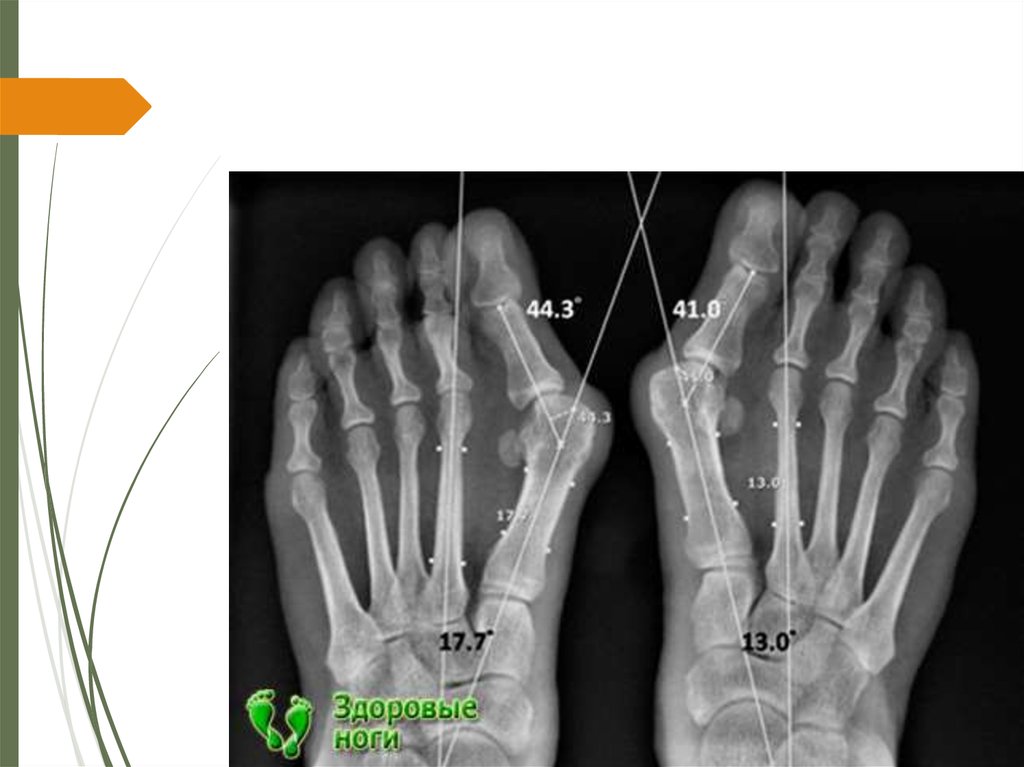

15. Методики рентгенологического обследования

Всем без исключения пациентам в дооперационном

периоде необходимо выполнять рентгенограммы стоп в

двух проекциях. Прямая проекция выполняется

следующим образом: расстояние от рентгеновской

трубки до обследуемой стопы должно быть равно 1

метру, что позволяет точно определить размеры

плюсневых костей и делается под углом 15 градусов

относительно вертикальной плоскости, что в конечном

итоге позволяет получить строгую перпендикулярную

проекцию к плюсневым костям

Все рентгенограммы необходимо выполнять с

нагрузкой, так как разница между значением углов

на рентгенограммах с нагрузкой, по сравнению с

рентгенограммами без нагрузки, может достигать

20%. (Карданов А.А. с соавт., 2008). После

выполнения рентгенограмм на них необходимо

выполнить измерения величин необходимых для

предоперационного планирования.

Отмечаются следующие показатели, которые

являются наиболее информативными для

планирования оперативного лечения: